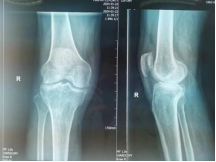

髋、膝、肩、肘、踝等疾病的关节置换手术。特色:先天性髋关节发育不良全髋关节置换术,股骨头坏死全髋关节置换术。膝关节骨性关节炎全膝关节置换术,髋膝关节置换术后假体松动、感染翻修术。

保髋、保膝手术:股骨头坏死髓心减压术、胫骨高位截骨矫形术、内外侧单髁置换术、关节镜下关节清理术。